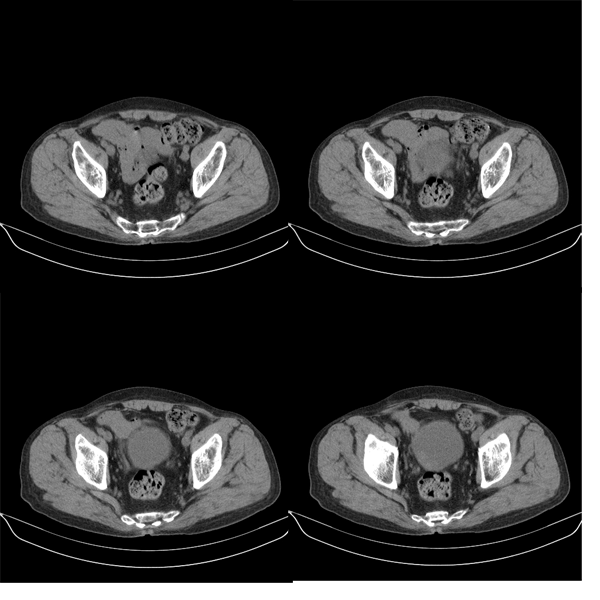

m79y自述30年前做过疝手术,20年前间断出现尿血,每次经抗炎治疗后即好转,近一月来又出现尿血但抗炎后仍尿血.现做双肾+盆腔ct:

盆腔5mmct扫描

该病人年龄过大故放弃了增强.ct做完后本人检查病人发现病人耻骨联合上稍偏右见一突出的包块影,质地柔软,平卧位手压后可以回缩.站立位突出明显!

膀胱三角区右侧可见较大软组织肿块,分叶状,内可见更低密度区,ct做完后本人检查病人发现病人耻骨联合上稍偏右见一突出的包块影,质地柔软,平卧位手压后可以回缩.站立位突出明显!考虑腹股沟斜疝,疝内容物为膀胱.膀胱内肿物考虑1炎性赘生物2平滑肌肉瘤(有多年血尿史,本次加重且抗炎不好转)3膀胱癌

盆腔超级经典病例--膀胱癌+膀胱疝出引起的右侧腹股沟斜疝膀胱疝,果然名不虚传!谢谢楼主!   “m79y自述30年前做过疝手术,20年前间断出现尿血,每次经抗炎治疗后即好转”,这是因为膀胱的疝入甚至短暂或部分嵌顿以及由此引起的炎症所造成,当然抗炎治疗后好转;“近一月来又出现尿血但抗炎后仍尿血”,这就是膀胱癌在作怪了,呵呵。

1、右侧腹股沟斜疝,疝内容物为膀胱;2、膀胱右后壁肿块,考虑膀胱癌

可能是膀胱癌+滑疝